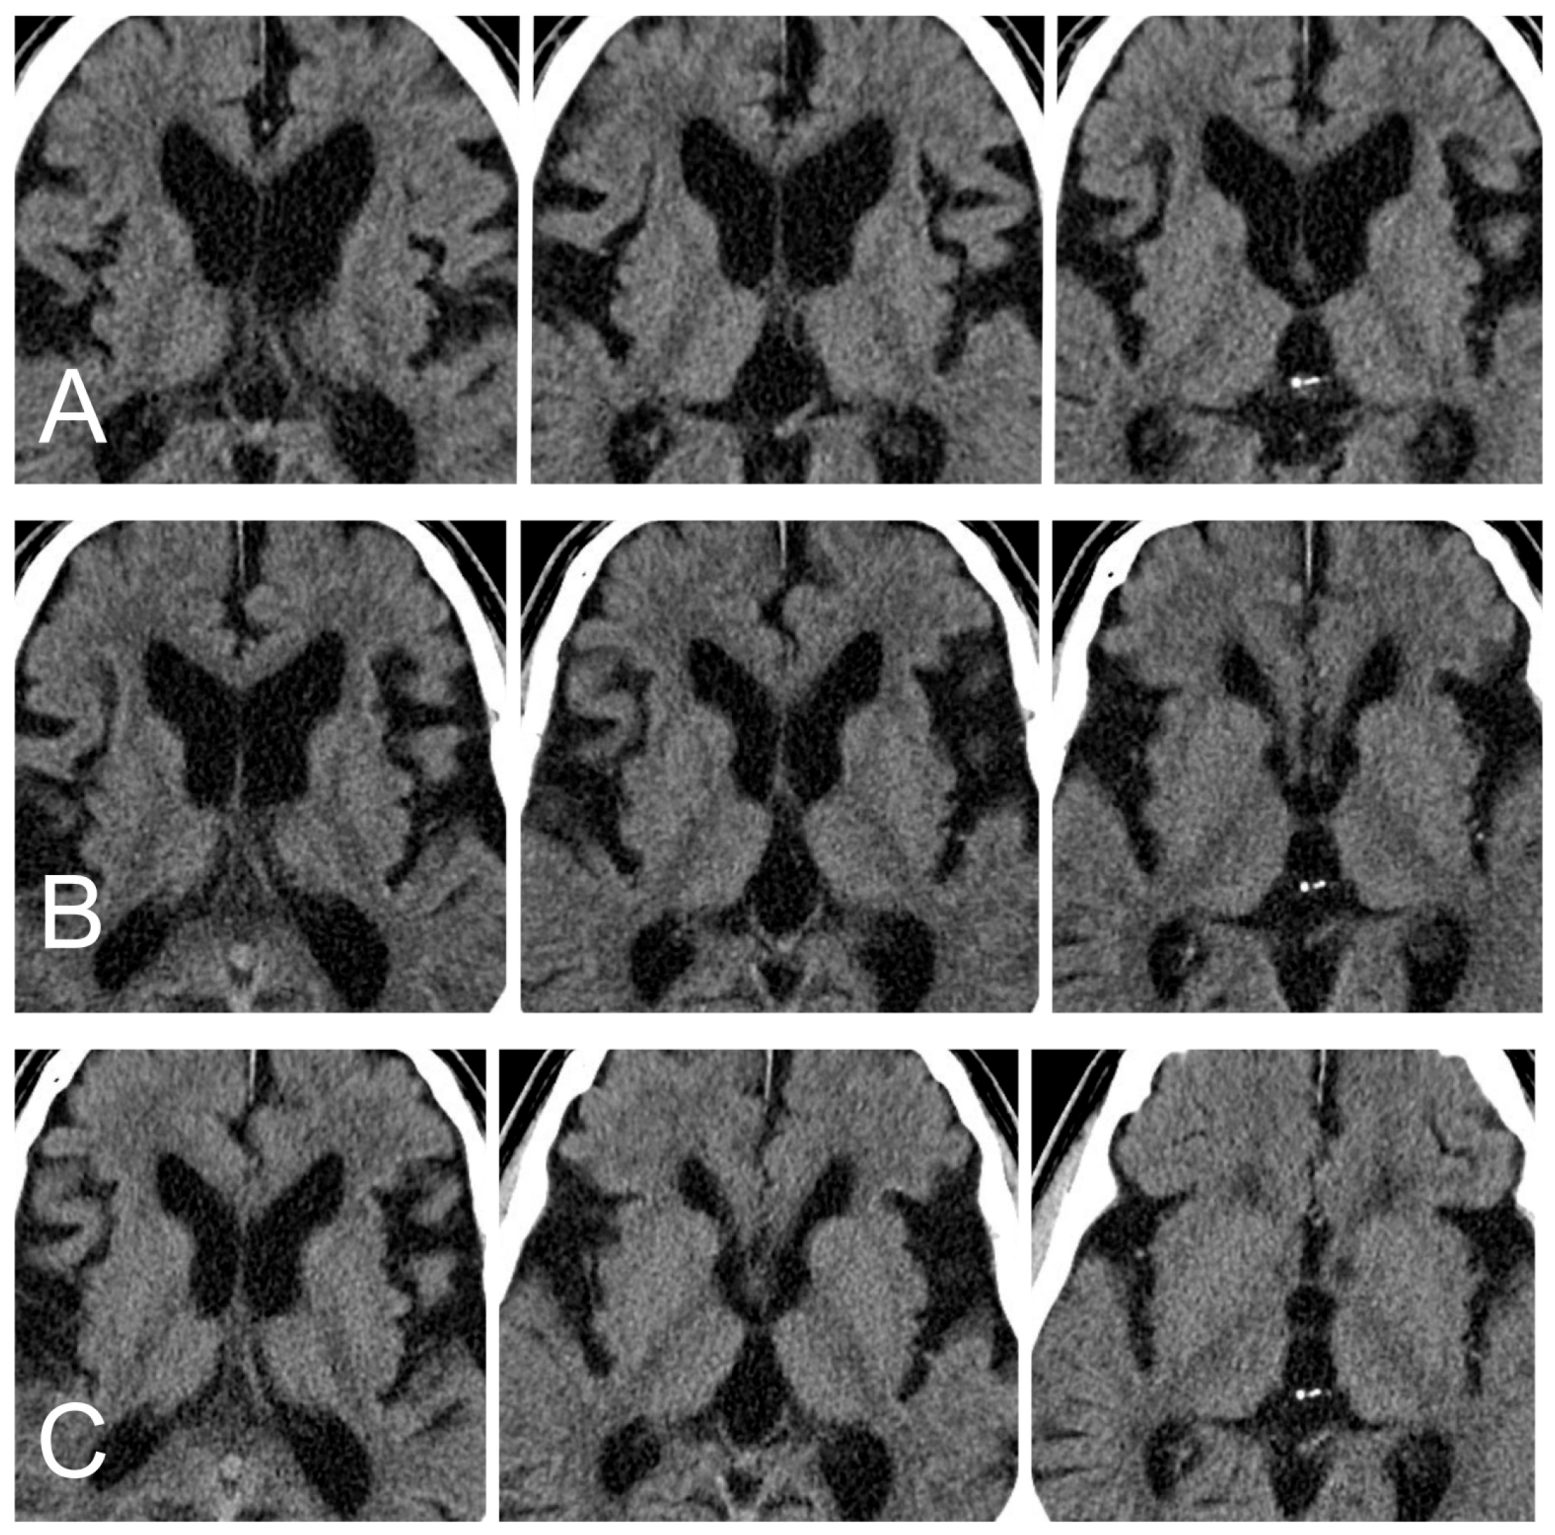

- It avoided the kinking of the lumbar spinal catheter in the thecal sac. In our experience, spinal catheter entanglement or twisting occurred in about 10%–15% cases, but we were able to correct it immediately under fluoroscopic guidance (Figure 5).